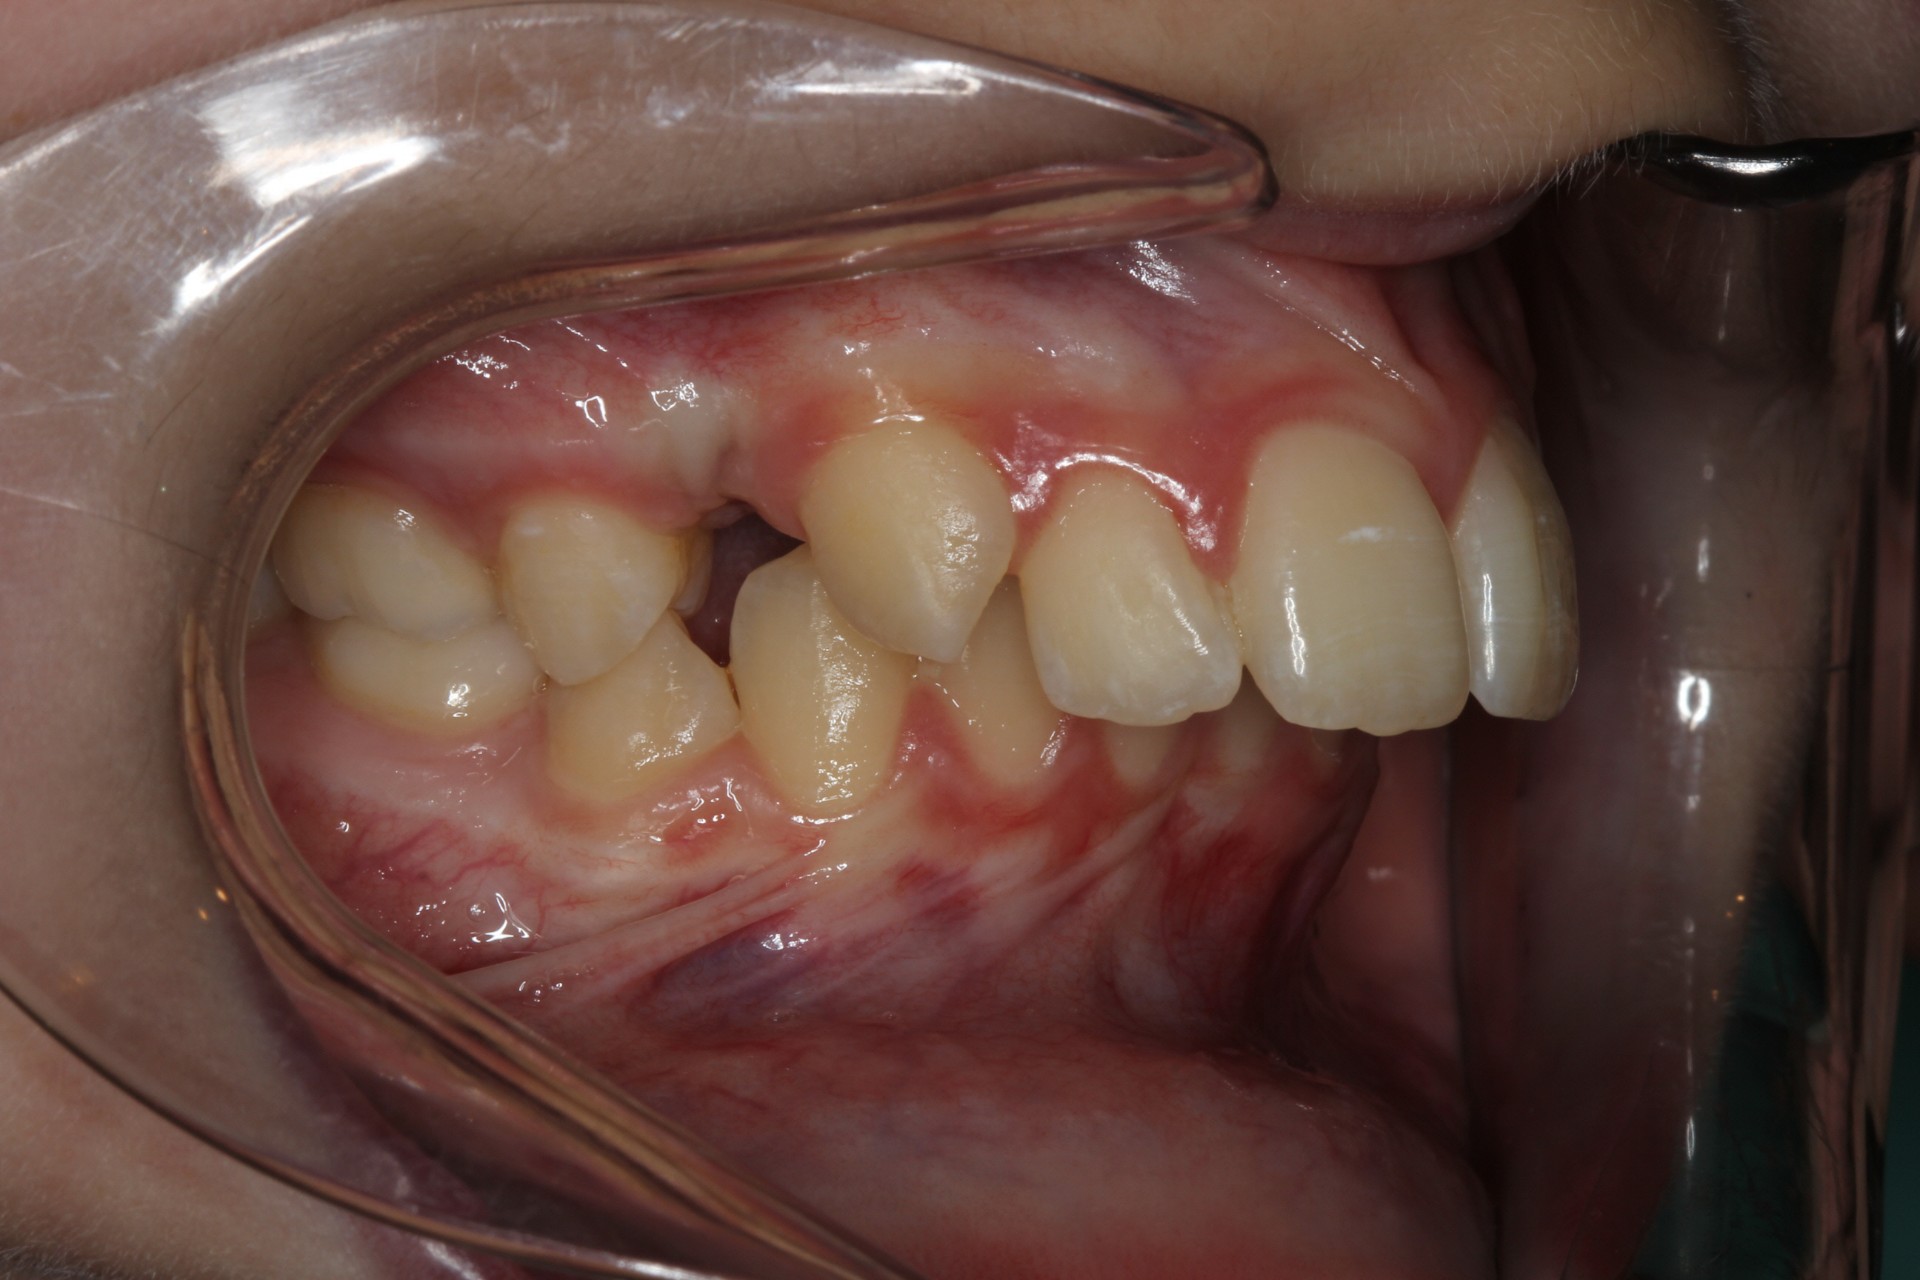

Protruding front teeth with midline diastema – Child case